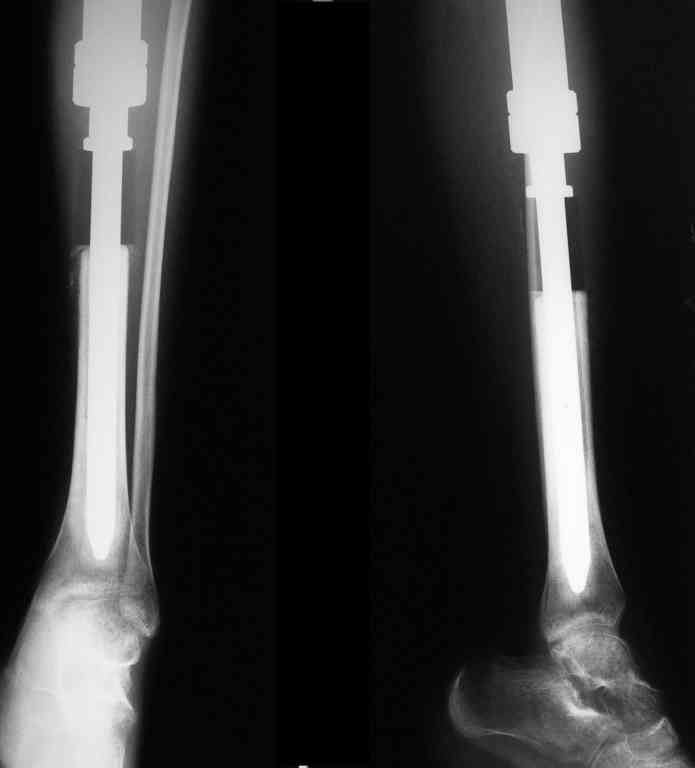

Уважаемые коллеги! Хотелось бы узнать ваше мнение о тактике лечения пациентки 16 лет, диагноз - б-нь Гоше I типа, состояние после резекции проксимальных 2/3 левой большеберцовой кости, тотального эндопротезирования ЛКС онкологическим эндопротезом, перипротезная инфекция.

Протез установлен год назад, в течение 8 месяцевфункционируют свищи, сообщающиеся с компонентами эндопротеза.

Планируется оперативное лечение, которое ранее не выполнялось по причине низких показателей крови (Тц-30, Нв-50, Лц-2,5) после химиотерапии. В настоящее время показатели крови постепенно нормализуются и встаёт вопрос о тактике хирургического лечения.

Пациентку беспокоят боли в нижней трети голени при физической нагрузки.